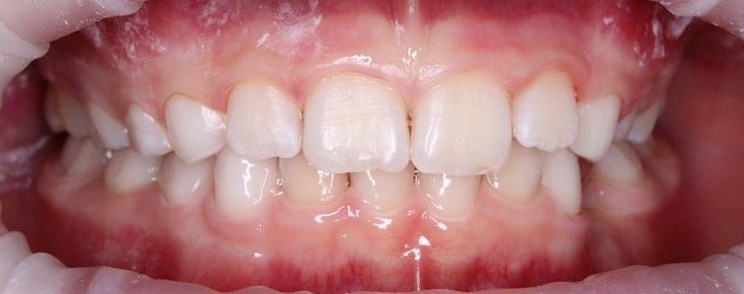

Стоматологическая клиника ГРАНАТ

Чистка зубов Air-flow